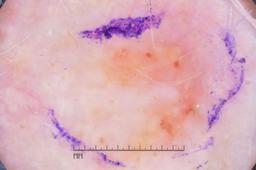

{

"age_approx": 40,

"anatom_site_general": "lower extremity",

"concomitant_biopsy": true,

"dermoscopic_type": "contact non-polarized",

"diagnosis_1": "Benign",

"diagnosis_2": "Benign melanocytic proliferations",

"diagnosis_3": "Nevus",

"diagnosis_confirm_type": "histopathology",

"image_type": "dermoscopic",

"lesion_id": "IL_0404349",

"melanocytic": true,

"sex": "female"

}